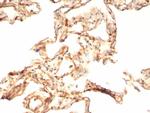

IL-6 (Interleukin-6)/Interferon beta-2 (Hybridoma Growth Factor) Antibody in Immunohistochemistry (Paraffin) (IHC (P))

Formalin-fixed, paraffin-embedded human COVID positive lung stained with IL-6 Mouse Monoclonal Antibody (IL6/4643) at 2 µg/mL. HIER: Tris/EDTA, pH9.0, 45 min. 2°C: HRP-polymer, 30 min. DAB, 5 min. {{ $ctrl.currentElement.advancedVerification.fullName }} 验证信息 View more